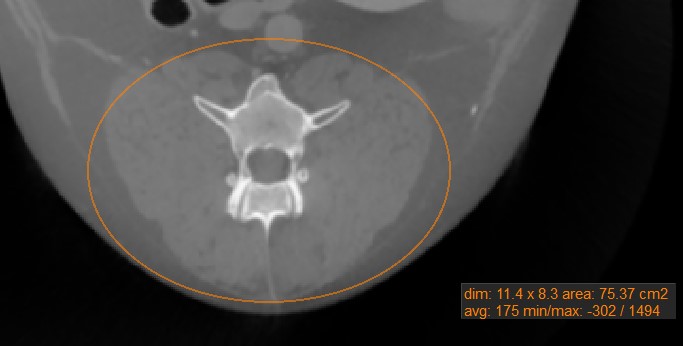

Oval¶

Select the Oval

tool and assign it to one of the available mouse buttons. Start the measurement by pressing on the active image slice and drag the mouse to obtain an oval shape. Release the mouse when satisfied

with the size of the marked area.

All available measurement values are displayed alongside the measurement.

Modify the marked area by moving one of the four points describing the rectangle around the oval shape using the Default

tool.